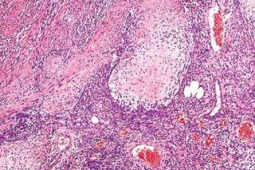

Dostępne są już pierwsze doniesienia potwierdzające wysoką skuteczność sztucznej inteligencji opartej na połączonych, splotowych sieciach neuronowych (ang. convolutional neural networks) w diagnostyce zmian melanocytowych. Ostatnio w JAMA Dermatology ukazała się publikacja przedstawiająca skuteczność sztucznej inteligencji w rozpoznawaniu raków skóry pozbawionych pigmentu (ang. nonpigmented skin cancers).

Sieć neuronowa została oparta na zbiorze danych z ponad 14 tys. zdjęć dermoskopowych lub wykonanych aparatem w dużym przybliżeniu przedstawiających raki skóry. Utworzoną sieć neuronową przetestowano na zbiorze 2072 przypadków oraz porównano wyniki sieci z wynikami uzyskanymi na tym samym zbiorze przez 95 lekarzy z różnych doświadczeniem w wykonywaniu dermoskopii (trzy grupy: < 3 lat doświadczenia - „początkujący”, 3-10 lat doświadczenia - „zaawansowani”, >10 lat doświadczenia - „eksperci”).

Obszar pod krzywą (ang. Area Under the Curve) był wyższy w przypadku sieci neuronowej niż w przypadku ludzi (odpowiednio: 0,742; 95% CI: 0,729-0,755 vs. 0,695; 95% CI: 0,676-0,713; p < 0,01). Sieć neuronowa osiągnęła wyższą skuteczność w postawieniu konkretnej diagnozy w porównaniu ze wszystkimi lekarzami (odpowiednio: 37,6% vs. 33,5%; p = 0,001), ale w porównaniu z ekspertami w dermoskopii różnica była nieistotna statystycznie (sieć vs. eksperci: 37,3% vs. 40,0%; p = 0,18), co wskazuje, że trafność diagnoz stawianych przez model sztucznej inteligencji dorównywał najbardziej doświadczonym dermatologom.

Przedstawione wyniki eksperymentalnej sieci neuronowej dają nadzieję, na stworzenie precyzyjnego narzędzia diagnostycznego pomagającego klinicystom w rozpoznawaniu raków skóry.